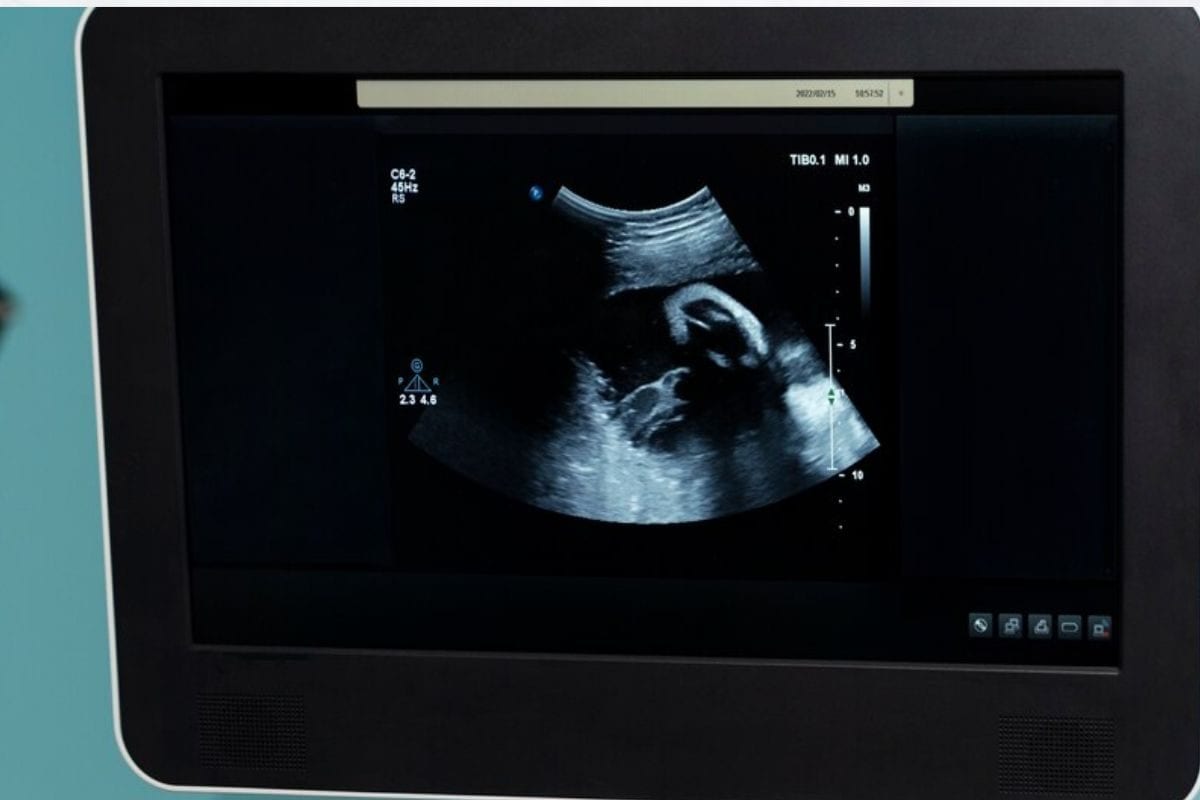

निःशुल्क अल्ट्रासाउंड: इलाज का तरीका बहुत मुश्किल हो गया है। एक बार डॉक्टर के पास जाने पर मोटा नकद खर्च होता है। निर्णायक पर परीक्षण जो हजारों के होते हैं। अल्ट्रासाउंड के लिए भी मोटा नोट कर्च किया हुआ हीरा है। लेकिन अब आपको मूल्यांकन लेने की आवश्यकता नहीं है। आप मुफ़्त में भी अल्ट्रासाउंड करा सकते हैं। आइये जानते हैं कैसे.

गरीब मरांडी गर्भवती महिलाओं का इलाज के अभाव में काफी संतृप्त का सामना करना पड़ता है। वो अल्ट्रासाउंड और सोनोग्राफी नहीं कराधान हैं। ऐसे में सरकार ने महिलाओं को फ्री अल्ट्रासाउंड करने के लिए एक स्कॉड शुरू किया है। नाम है ए.एन.सी चेकअप योजना। जो महीने में चार दिन लागू होता है. लोक 18 से बात करते हुए चिकित्सा प्रभारी कैप्टन रामबदन राजभर ने कहा कि सरकार द्वारा महिलाओं के लिए ए.एन.सी. चेकअप योजना शुरू की गई है। इस योजना के अंतर्गत गर्भवती महिलाओं का कुछ डेस्टिनेशन डेस्टिनेशन पर निःशुल्क अल्ट्रासाउंड डॉक्युमेंट दिया जा रहा है।

यह कुछ ऐसा ही है जहां पर महीने में चार दिन होते हैं। अल्ट्रासाउंड के लिए आपको मनोवैज्ञानिक स्वास्थ्य के मोहम्मदाबाद गोहाना से कोड प्राप्त करना होगा। नंबर बनाने के बाद यह कर कोड आप यदि अल्ट्रासाउंड किए गए अल्ट्रासाउंड सेंटर पर जाते हैं, तो वहां आपका अल्ट्रासाउंड किया जाएगा। जिस अल्ट्रासाउंड जांच के लिए आपको 700 से 800 हजार रुपये तक का भुगतान करना होगा, वह जांच में आपका बिल्कुल नकली करवा सकता है।

बी आर टी आर अल्ट्रासाउंड सेंटर, क्रोम डायग्नोस्टिक सेंटर और सुपर लाइफ अल्ट्रासाउंड सेंटर पर आप मुफ्त जांच कर सकते हैं। लेकिन जांच से पहले आपको चिकित्सकीय स्वास्थ्य केंद्र पर संपर्क नंबर लगाकर क्यूआर कोड प्राप्त करना होगा। यह हर महीने की 1 तारीख, 9 तारीख, 16 तारीख और 24 तारीख को अलविदा कहा गया। अल्ट्रासाउंड सेंटरों पर मुफ्त में काम किया जाता है। तो अब ऐसे में आपको अल्ट्रासाउंड कराने के लिए पैसे देने की कोई जरूरत नहीं है। आप सैमसंग से क्यूआर कोड प्राप्त करके तीन स्थानों पर अपना निशुल के अल्ट्रासाउंड करा सकते हैं।